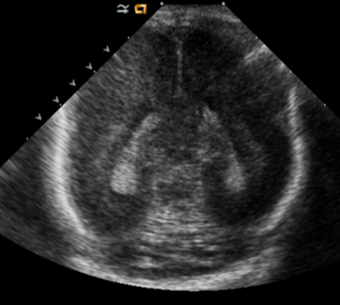

Germinal matrix hemorrhage (Only in the premature infants): Please do not answer if the patient is a full term.

There is a germinal matrix hemorrhage, consistent with a grade I hemorrhage. [Yes/No]

There is an intraventricular extension consistent with a grade II hemorrhage. [Yes/No]

There is an intraventricular extension with the dilatation of ventricles, consistent with a grade III hemorrhage. [Yes/No]

There is an intra-parenchymal extension, consistent with grade IV hemorrhage. [Yes/No]

Brain

The brain is immature. [Yes/No]

There is under-sulcation and open sylvian fissures. [Yes/No]

There is/are multiple hypoechoic areas in the periventricular white matter. [Yes/No]

There is/are multiple hyperechoic areas in the periventricular white matter. [Yes/No]

There is diffuse cerebral edema with diffusely increased echogenicity of the brain parenchyma and loss of grey white matter differentiation. [Yes/No]

The thalami/basal ganglia are hypoechoic. [Yes/No]

There is periventricular calcification. [Yes/No]

There is intra-parenchymal calcification. [Yes/No]